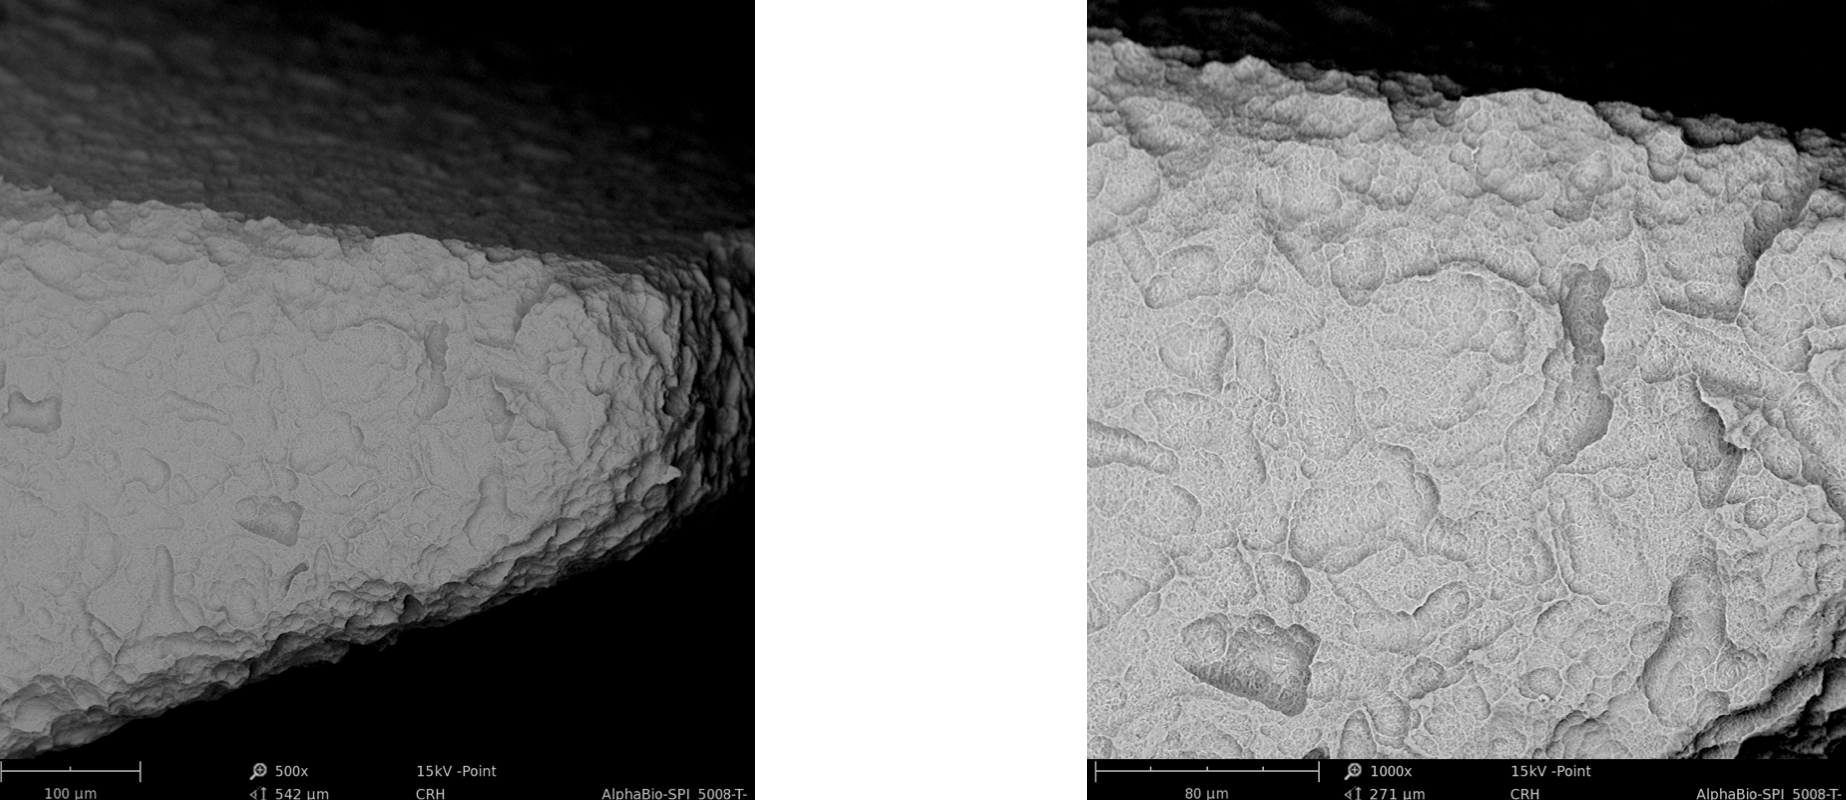

3.2 Surface-Topography - Material Contrast Images (Thread)

Surface-Topography - Material Contrast Images (Thread)

3.3 Surface-Topography - Material Contrast Images (Body)

Surface-Topography - Material Contrast Images (Body)